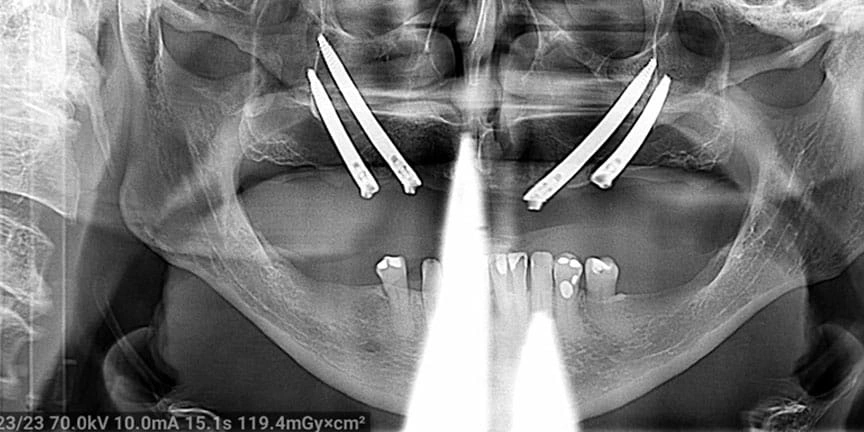

Severe Bone Loss